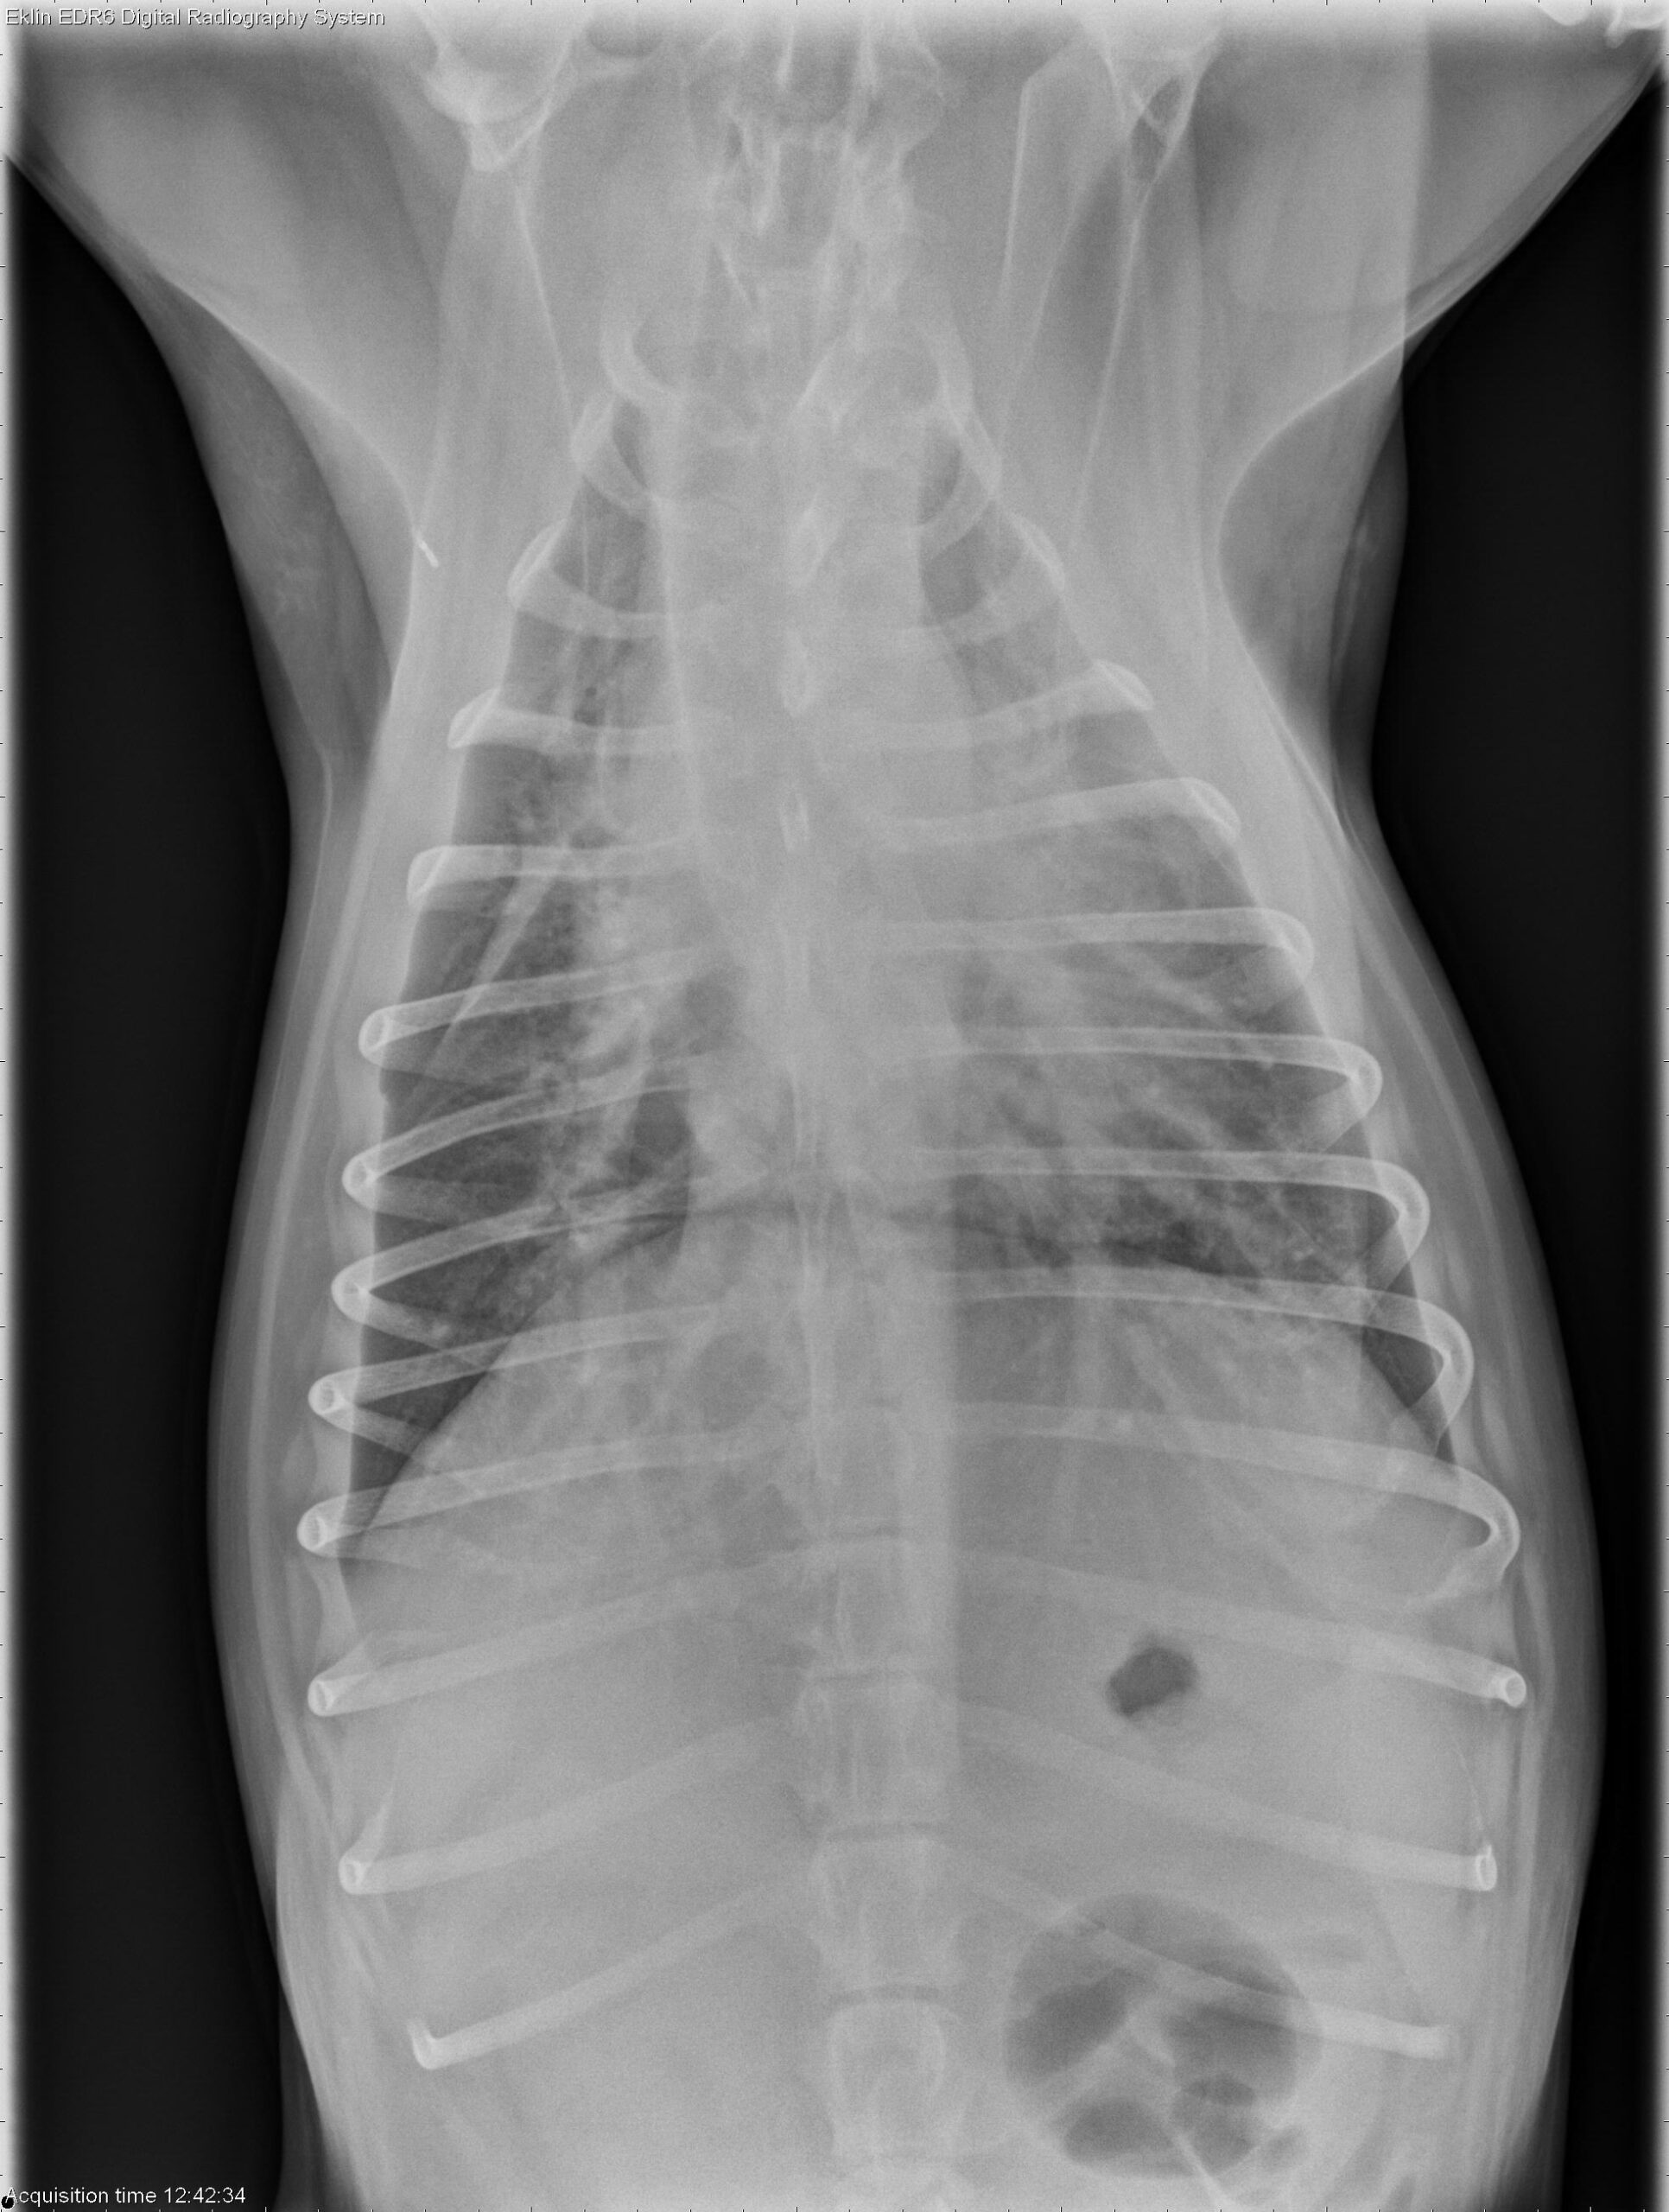

Below you’ll find the 4 X-ray images of the thorax. Use the arrows to scroll through, or click on the image to enlarge.

Thorax: There is increased soft tissue opacity within the pleural space, with retraction of the lung lobes and partial silhouetting with the cardiac silhouette, consistent with pleural effusion. A patchy broncho-interstitial pattern is present in the lungs. The cardiovascular structures appear normal.

Abdomen: The abdomen is distended with poor peritoneal detail. The liver and spleen are enlarged with rounded margins. The colon is moderately distended with gas. The small intestines appear normal. The urinary tract is poorly visualized.